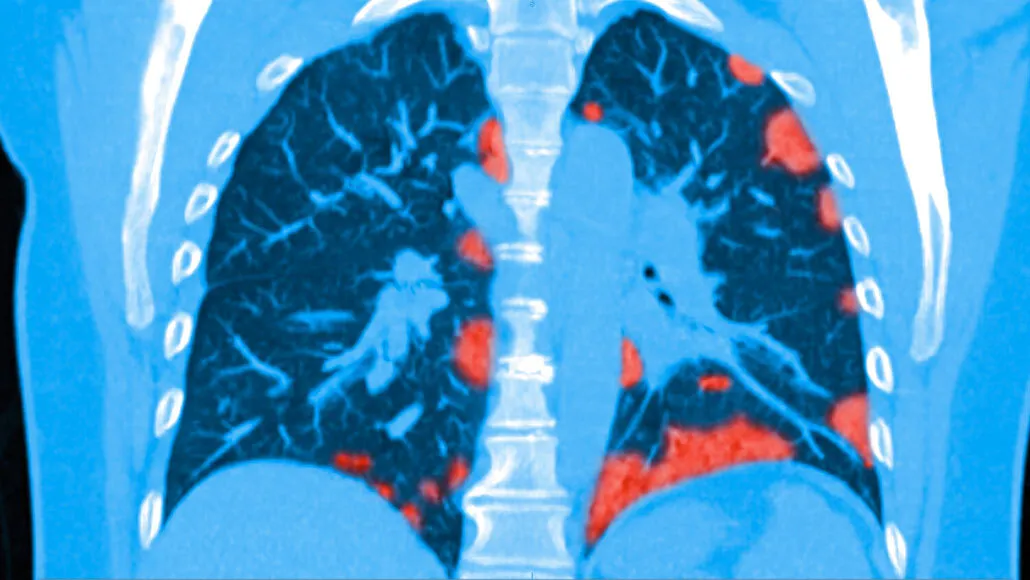

I then update this spreadsheet that is the attached screen shot

We ONLY hear from the BIASED MSM regarding the deaths.... 118,741... BUT as far as the people that have survived? ZERO. Nothing!

Over 2,178,977 or 99.25% of the cases were mild, not hospitalized.

94% of all CASES have recovered...survived... So why haven't we heard this?